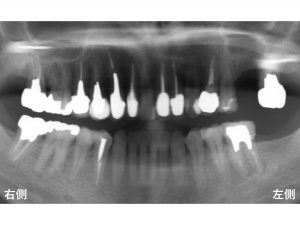

以下が初診時です。

上顎左側奥から2番目が欠損しています。

以下が治療後です。

長いインプラントを埋入することができました。

当医院で使用しているインプラントは、世界でもっとも信頼性の高いインプラントの一つであるストローマンインプラント です。